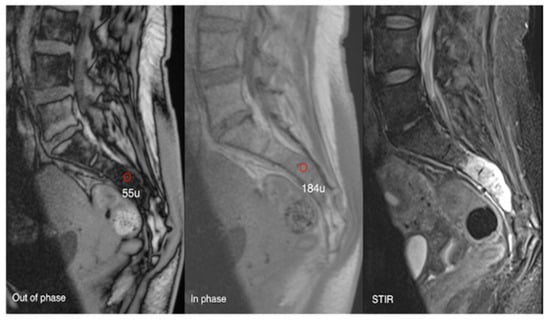

Figure 17.

Aggressive sacral haemangioma with soft tissue mass. Out-of-phase, in-phase, and STIR sagittal MRI spine as labelled on images (bottom left), showcasing the expansile nature of the lesion but also the internal fat content as demonstrated by >20% signal dropout of signal intensity values (55 SI vs. 184 SI) on the out-of-phase vs. in-phase sequence.